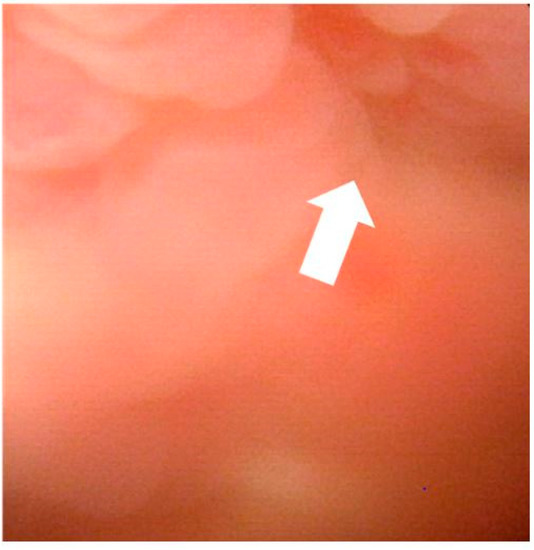

2. Case Report